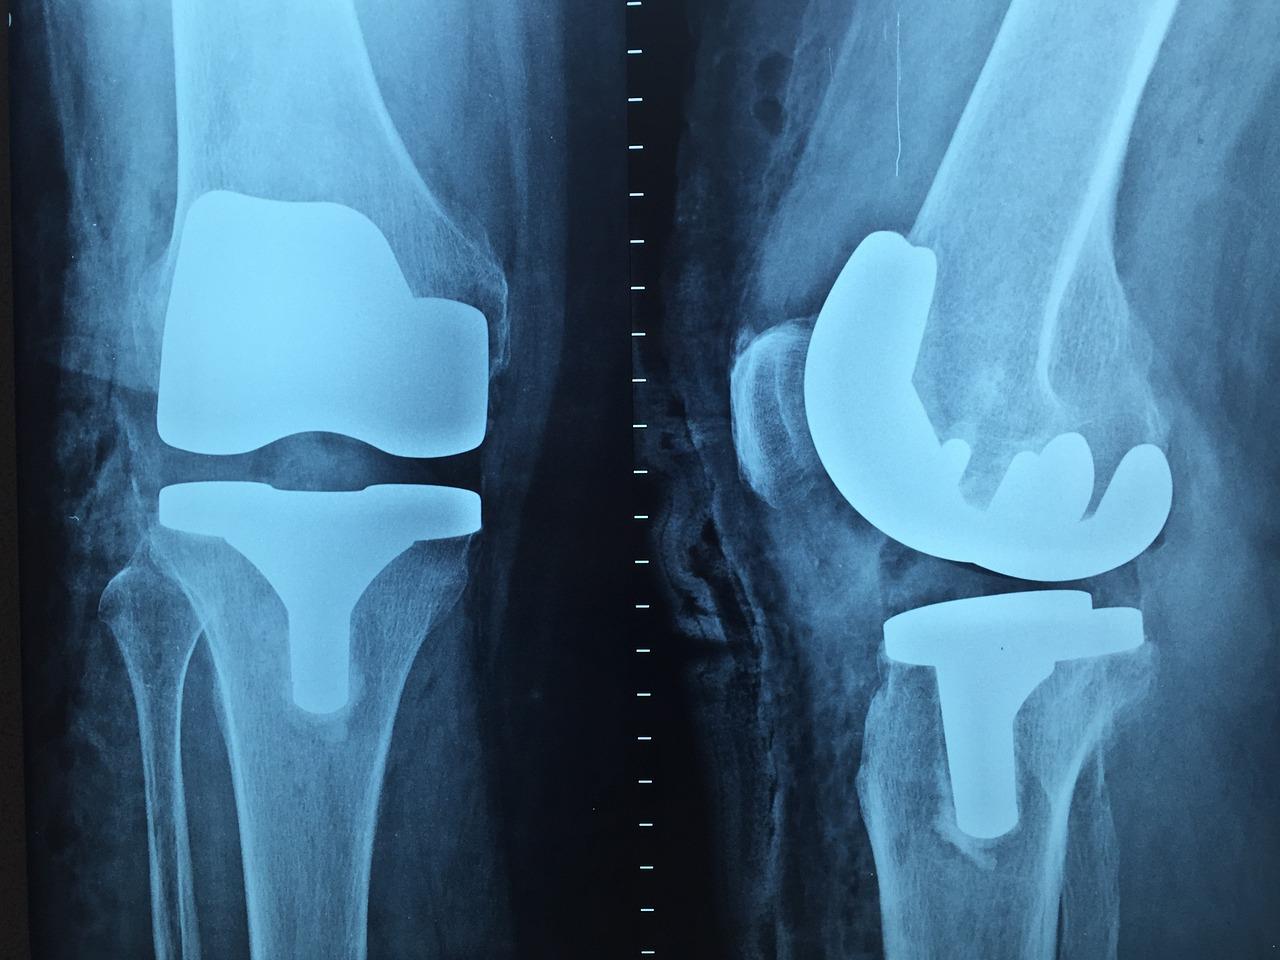

De orthopedie in Heerlen maakt gebruik van geavanceerde technologieën en innovatieve benaderingen om de diagnose, behandeling en revalidatie van orthopedische aandoeningen te verbeteren. Deze technologieën variëren van geavanceerde beeldvormingstechnieken en robotica tot minimaal invasieve chirurgische procedures en op maat gemaakte prothesen en implantaten.

Door gebruik te maken van deze cutting-edge technologieën kunnen orthopedische specialisten in Heerlen nauwkeurigere diagnoses stellen, meer gepersonaliseerde behandelplannen opstellen en betere resultaten behalen voor hun patiënten. Dit kan leiden tot kortere hersteltijden, verminderde complicaties en verbeterde langetermijnresultaten voor patiënten met orthopedische aandoeningen.

De orthopedische zorg in Heerlen wordt voortdurend verbeterd door de integratie van innovatieve technologieën en geavanceerde apparatuur die zijn ontworpen om de nauwkeurigheid, efficiëntie en veiligheid van orthopedische procedures te verbeteren. Deze technologieën variëren van geavanceerde beeldvormingssystemen en robotgestuurde chirurgische platforms tot 3D-printing van op maat gemaakte implantaten en protheses.

Door gebruik te maken van deze geavanceerde technologieën kunnen orthopedische chirurgen in Heerlen nauwkeuriger en minder invasieve procedures uitvoeren, waardoor de hersteltijd van de patiënt wordt verkort en de kans op complicaties wordt verminderd. Bovendien kunnen op maat gemaakte implantaten en protheses een betere pasvorm en functionaliteit bieden, wat resulteert in een verbeterde kwaliteit van leven voor de patiënt.